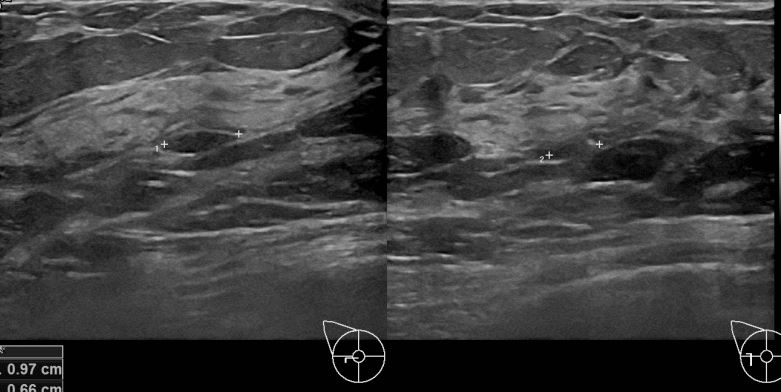

6개월전 부터 유방의 통증이 있어 내원하신 50대 여성분으로 초음파검사이후

의심스러운 좌측의 결절 조직검사후 유방암으로 진단되셨습니다.